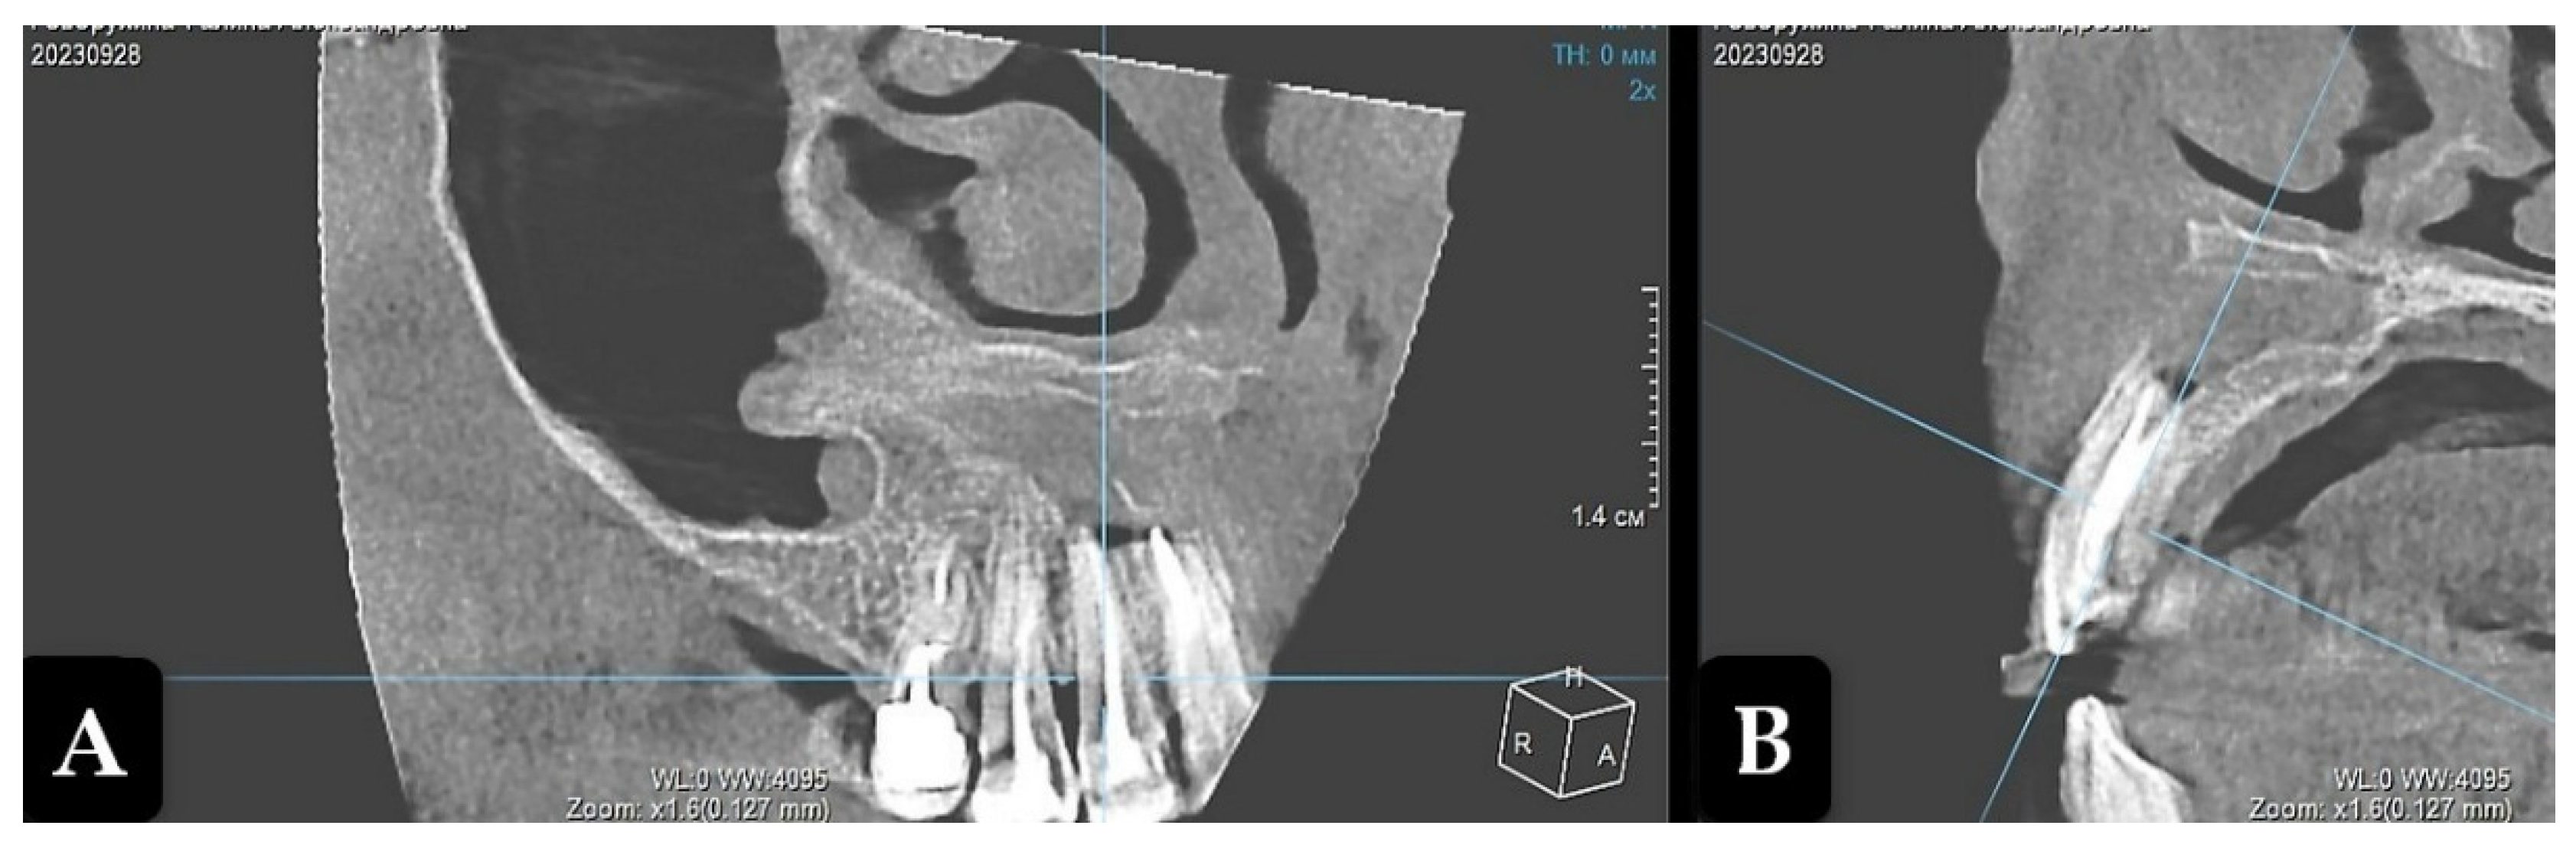

Long-term results were evaluated for up to 2 years. The patient did not experience any problems from the oral and maxillofacial organs. One year after the operation, CBCT visualized the vague contours of the residual cavity filled with bone trabeculae, which had significantly decreased compared to the preoperative findings. Parietal bone regeneration was detected, while no signs of organotypicity were recorded in the center (Figure 4).

Figure 4. Cone-beam computed tomography. Residual bone cavity 1 year after enucleation of radicular cyst (projection of tooth 12). A: Frontal projection; B: Sagittal projection.